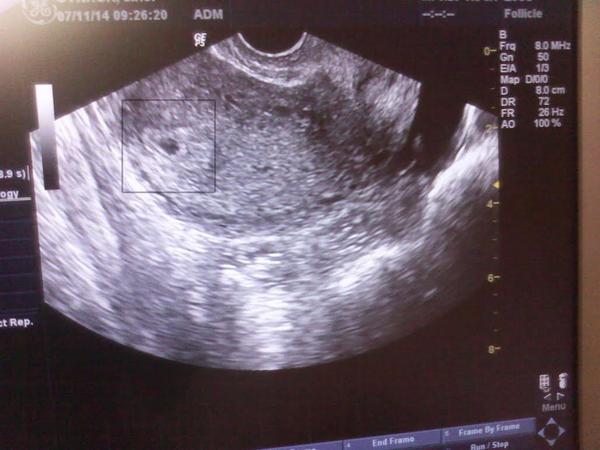

ahojte, takze uz som spat 🙂 na utz bolo vidiet malu dutinku 🙂 🙂 aj som si ju sfotila... doktorka sice vravela ze je to este velmi malicke, ze je to skoro .. a ze vylucit mimomaternicove sa da az ked zacne bit srdiecko... no zodpoveda to hodnotam HCG ...mam prist tak za 7 - 10 dni, uz by malo bit 🙂 .. brali mi aj krv a budem vediet vysledky az okolo pol druhej 🙂

PS: chcete vidiet fotecku? aspon posudite ..